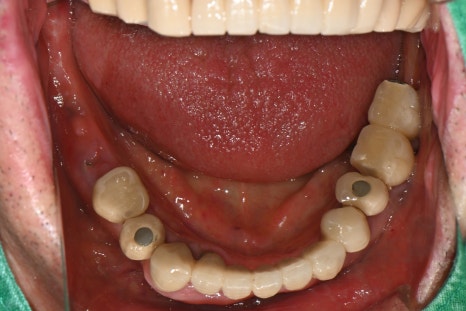

Right photo: The lower teeth had a missing crown and a broken implant, so overall reconstruction was needed.

Right photo: The final prosthesis was accurately secured to the implant placed in the extracted site.